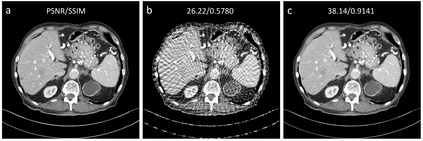

Sparse-view computed tomography (CT) can be used to reduce radiation dose greatly but is suffers from severe image artifacts. Recently, the deep learning based method for sparse-view CT reconstruction has attracted a major attention. However, neural networks often have a limited ability to remove the artifacts when they only work in the image domain. Deep learning-based sinogram processing can achieve a better anti-artifact performance, but it inevitably requires feature maps of the whole image in a video memory, which makes handling large-scale or three-dimensional (3D) images rather challenging. In this paper, we propose a patch-based denoising diffusion probabilistic model (DDPM) for sparse-view CT reconstruction. A DDPM network based on patches extracted from fully sampled projection data is trained and then used to inpaint down-sampled projection data. The network does not require paired full-sampled and down-sampled data, enabling unsupervised learning. Since the data processing is patch-based, the deep learning workflow can be distributed in parallel, overcoming the memory problem of large-scale data. Our experiments show that the proposed method can effectively suppress few-view artifacts while faithfully preserving textural details.